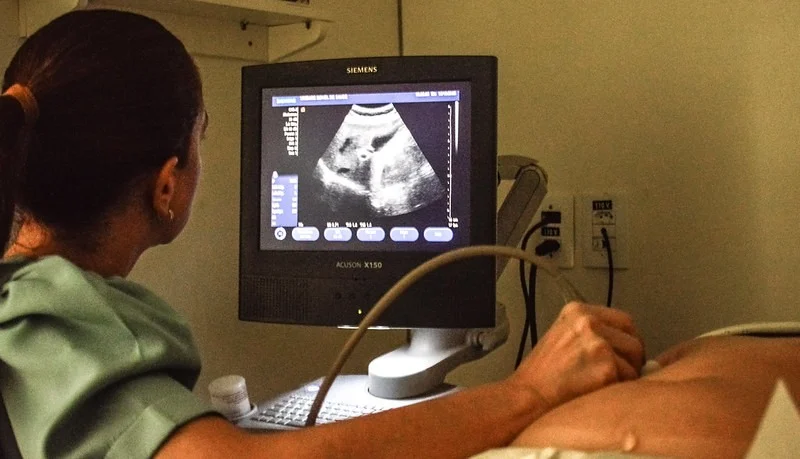

.Uma das Carretas da Saúde do Governo do Amazonas estará prestando atendimentos no bairro Japiim até quinta-feira (12), com a oferta de exames de mamografia e ultrassonografia. A unidade móvel está atendendo na área de estacionamento da Escola Estadual Nathália Uchôa, na avenida Waldomiro Lustoza, 350, zona sul de Manaus.

Os exames nas carretas de ultrassonografia e mamografia acontecem de segunda a sexta-feira, das 8h às 12h e das 13h às 17h. São oferecidas ultrassonografia de abdômen total, abdômen superior, tireoide, aparelho urinário, próstata via abdominal, além de ultrassonografias transvaginal e pélvica.